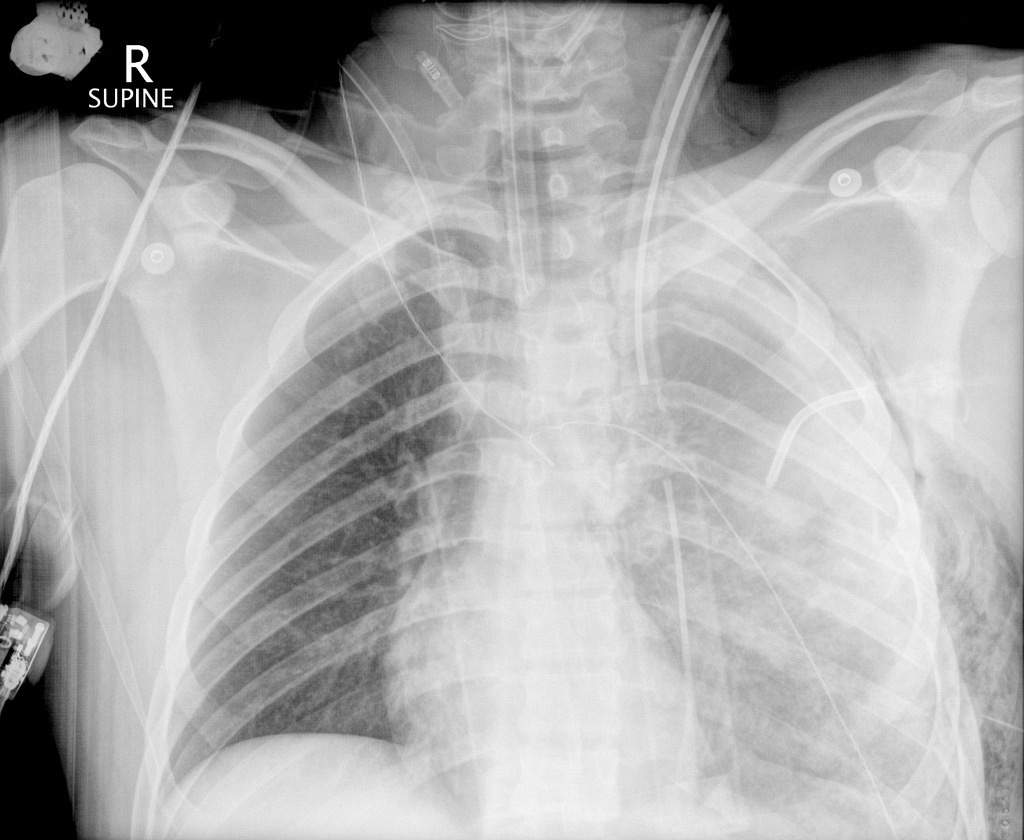

Чоловік 20 років, після дорожньо-транспортної пригоди на високій швидкості.

На рентгенограмі в прямій проекції в положенні лежачі спостерігається великий лівобічний гемоторакс. Середостіння імовірно зміщене вправо. Наявні двобічні переломи задніх ребер зі зміщенням. Підшкірна емфізема зліва. Катетер для дренування плевральної порожнини зліва у 2му міжребер‘ї.

Висновок: на рентгенограмі ОГК спостерігається політравма.